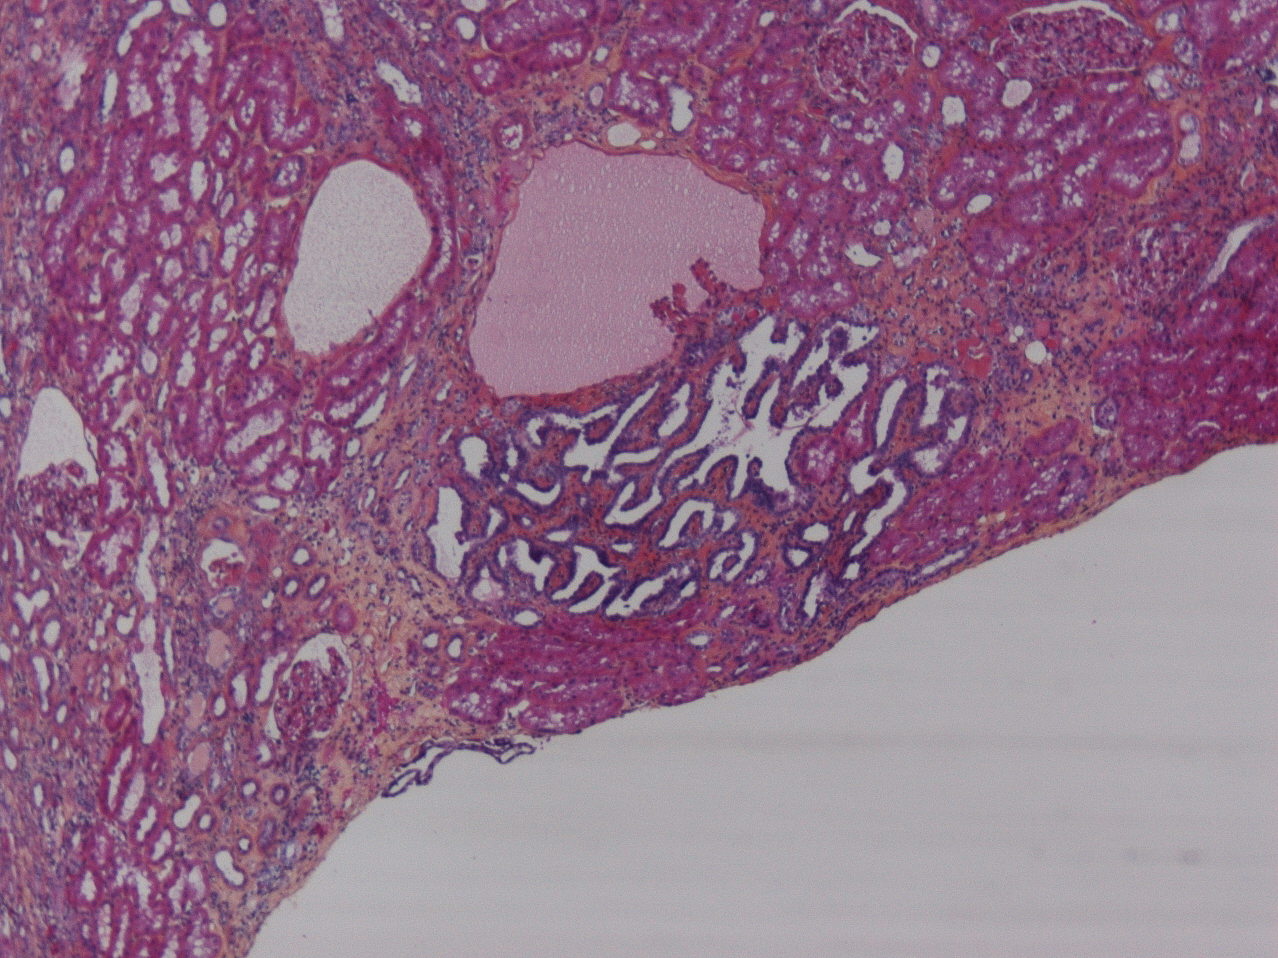

Consensus grade: I would not grade this tumor

adenoma